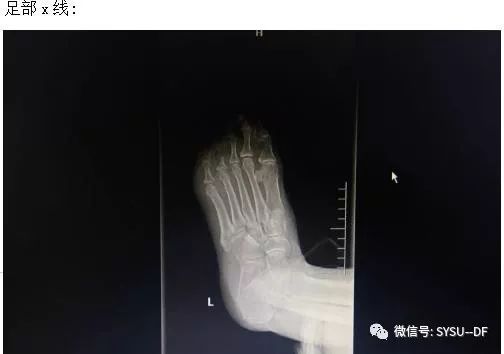

足部伤口情况详见下叙:

第一天伤口情况:左足底第五脚趾下方皮肤可见大小约2×1.5C M溃疡,基底为黄色腐肉及脓性分泌物,全足红肿,臭味,皮温升高,有触痛,无明显波动感,双侧股动脉、腘动脉搏动正常,双侧足背动脉搏动减弱。